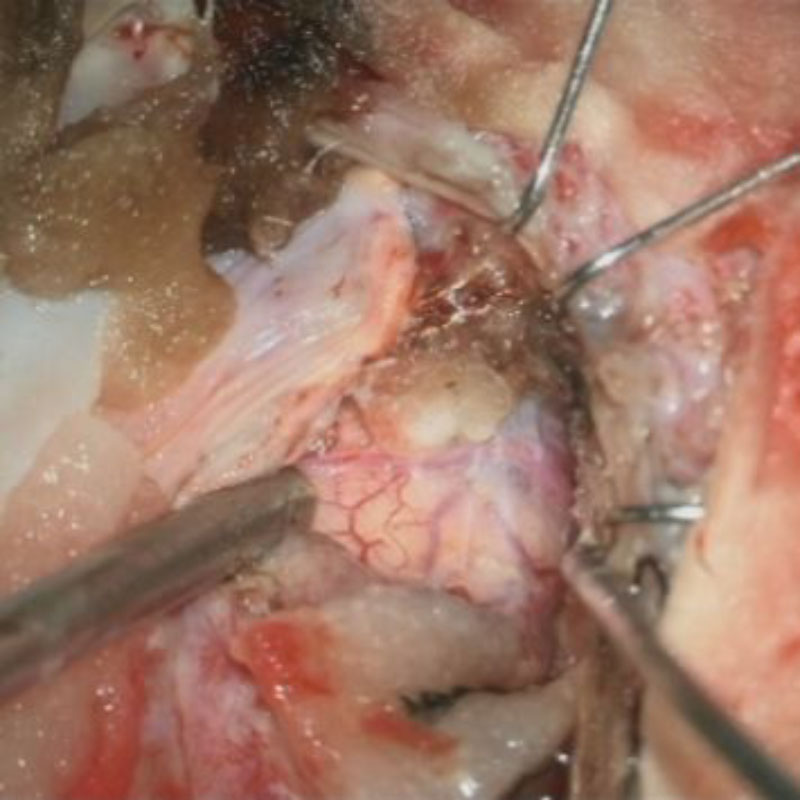

下垂体腺腫

頭蓋内腫瘍摘出術

No.’25_34 摘出 前

No.’25_34  摘出 中

No.’25_34 摘出 後